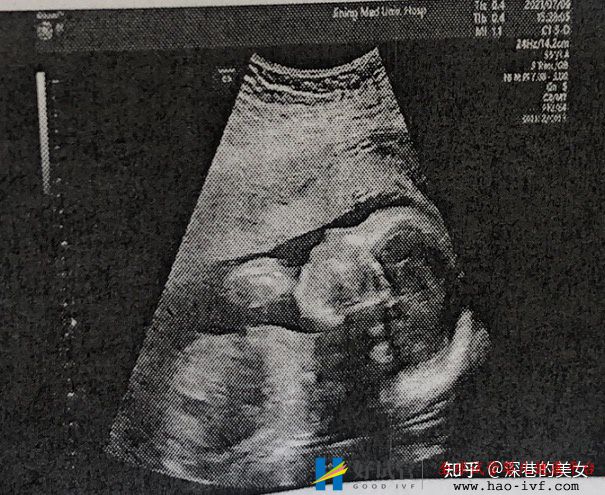

满心期待熬到24周了,以为可以去跟小家伙见一面了。结果我们医院是三级B超,没有四维彩超。所以就没有网上那种脸部照片。心里好失落啊。毕竟期待了那么久。虽然医生说着娃娃漂亮、下巴漂亮。但还是想看看。

没有忍住还是去私人医院给小家伙照了四维照片。

鼻梁的确高。哈哈